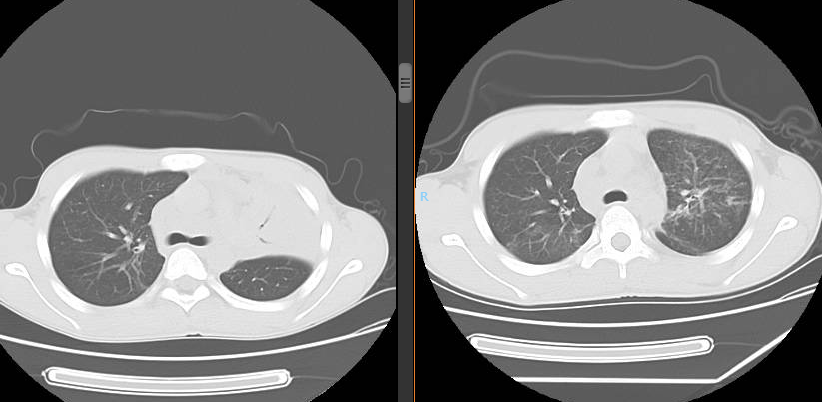

今年剛升入初二的小邰本應(yīng)該在學(xué)校緊張的學(xué)習(xí),卻因一場疾病飽受煎熬;小邰家住貴州省黔東南苗族侗族自治州,在3個(gè)月前小邰出現(xiàn)了夜間反復(fù)畏寒、發(fā)熱,日間活動(dòng)后感胸悶、氣促,時(shí)不時(shí)有干咳,不得不請(qǐng)假就診于當(dāng)?shù)蒯t(yī)院。 查胸部CT等相關(guān)檢查后明確診斷為“肺結(jié)核”,并開始服用抗結(jié)核藥。經(jīng)過規(guī)范治療后雖然不再發(fā)熱,但活動(dòng)后胸悶、氣促癥狀并無好轉(zhuǎn),于是再次就診當(dāng)?shù)蒯t(yī)院復(fù)查肺部CT檢出“左上肺不張”,小邰因此一直未能復(fù)學(xué),感到非??鄲?,但是病魔并沒有由此放過他,他感覺胸悶、氣促癥狀一直在加重,日?;顒?dòng)后需要休息很久才能緩解,于是經(jīng)當(dāng)?shù)蒯t(yī)院建議轉(zhuǎn)診至貴陽市公共衛(wèi)生救治中心(市五醫(yī)

肺科醫(yī)院)住院治療。 10月10日,我院內(nèi)鏡中心為小邰進(jìn)行了第一次支氣管鏡檢查,檢查提示小邰左肺上葉可以看見巨大新生物完全阻塞管腔,充分評(píng)估后,行手術(shù)治療,手術(shù)中應(yīng)用了活檢鉗、異物鉗、冷凍、高頻電刀、內(nèi)鏡下超聲探頭等方法,既保證了患者的安全,又達(dá)到了治療目的,通過三次手術(shù),終于將左上葉巨大腫塊清除掉了。術(shù)后1周復(fù)查胸部CT小邰左肺上葉復(fù)張開來,感覺胸悶、氣促癥狀明顯改善,患者家屬和內(nèi)鏡中心的醫(yī)護(hù)人員由衷為他感到開心。 左上葉巨大新生物阻塞管腔 治療后左上葉恢復(fù)通暢 高頻電消融治療 支氣管結(jié)核科普知識(shí) 在日常生活中大家可能經(jīng)常聽說肺結(jié)核,可是又有多少人知道支氣管結(jié)核呢?其實(shí)支氣管結(jié)核是肺結(jié)核的一種特殊類型,支氣管結(jié)核起病緩慢,癥狀隱匿,缺乏特異性,主要表現(xiàn)為間斷咳嗽、咳痰等。因?yàn)榍捌诎Y狀不重,往往被患者所忽視,等病變逐漸增大,阻塞氣管、支氣管時(shí)可出現(xiàn)嚴(yán)重的呼吸困難、咯血、胸痛等癥狀,嚴(yán)重氣道狹窄甚至可能危及生命。支氣管結(jié)核的診斷需要行支氣管鏡的檢查來發(fā)現(xiàn),早期診斷、早期治療是決定預(yù)后的關(guān)鍵。中晚期出現(xiàn)纖維疤痕狹窄,往往療效不佳。支氣管結(jié)核在發(fā)病4~6個(gè)月內(nèi)支氣管狹窄發(fā)生率可達(dá)68%,隨著時(shí)間延長,并發(fā)癥發(fā)生率還將進(jìn)一步提高。嚴(yán)重的支氣管狹窄和阻塞可引起肺不張、反復(fù)感染、呼吸衰竭和窒息,為死亡的主要原因。故支氣管結(jié)核患者早期進(jìn)行支氣管鏡檢查、介入治療是十分有必要的,可以有效改善病情及預(yù)后,目前我中心內(nèi)鏡下介入治療包括病變支氣管藥物灌注治療、活檢清理、高頻電消融、冷凍切除、狹窄管腔內(nèi)支架置入、球囊擴(kuò)張、超聲支氣管鏡等。 早識(shí)早治,呼吸健康從關(guān)懷開始。通過支氣管鏡介入治療,我們致力于為患者提供最先進(jìn)的手段和關(guān)懷,確保在關(guān)鍵時(shí)刻護(hù)航呼吸健康。讓我們攜手,將關(guān)注和治療延伸至每個(gè)支氣管,為患者帶來更明朗的未來。